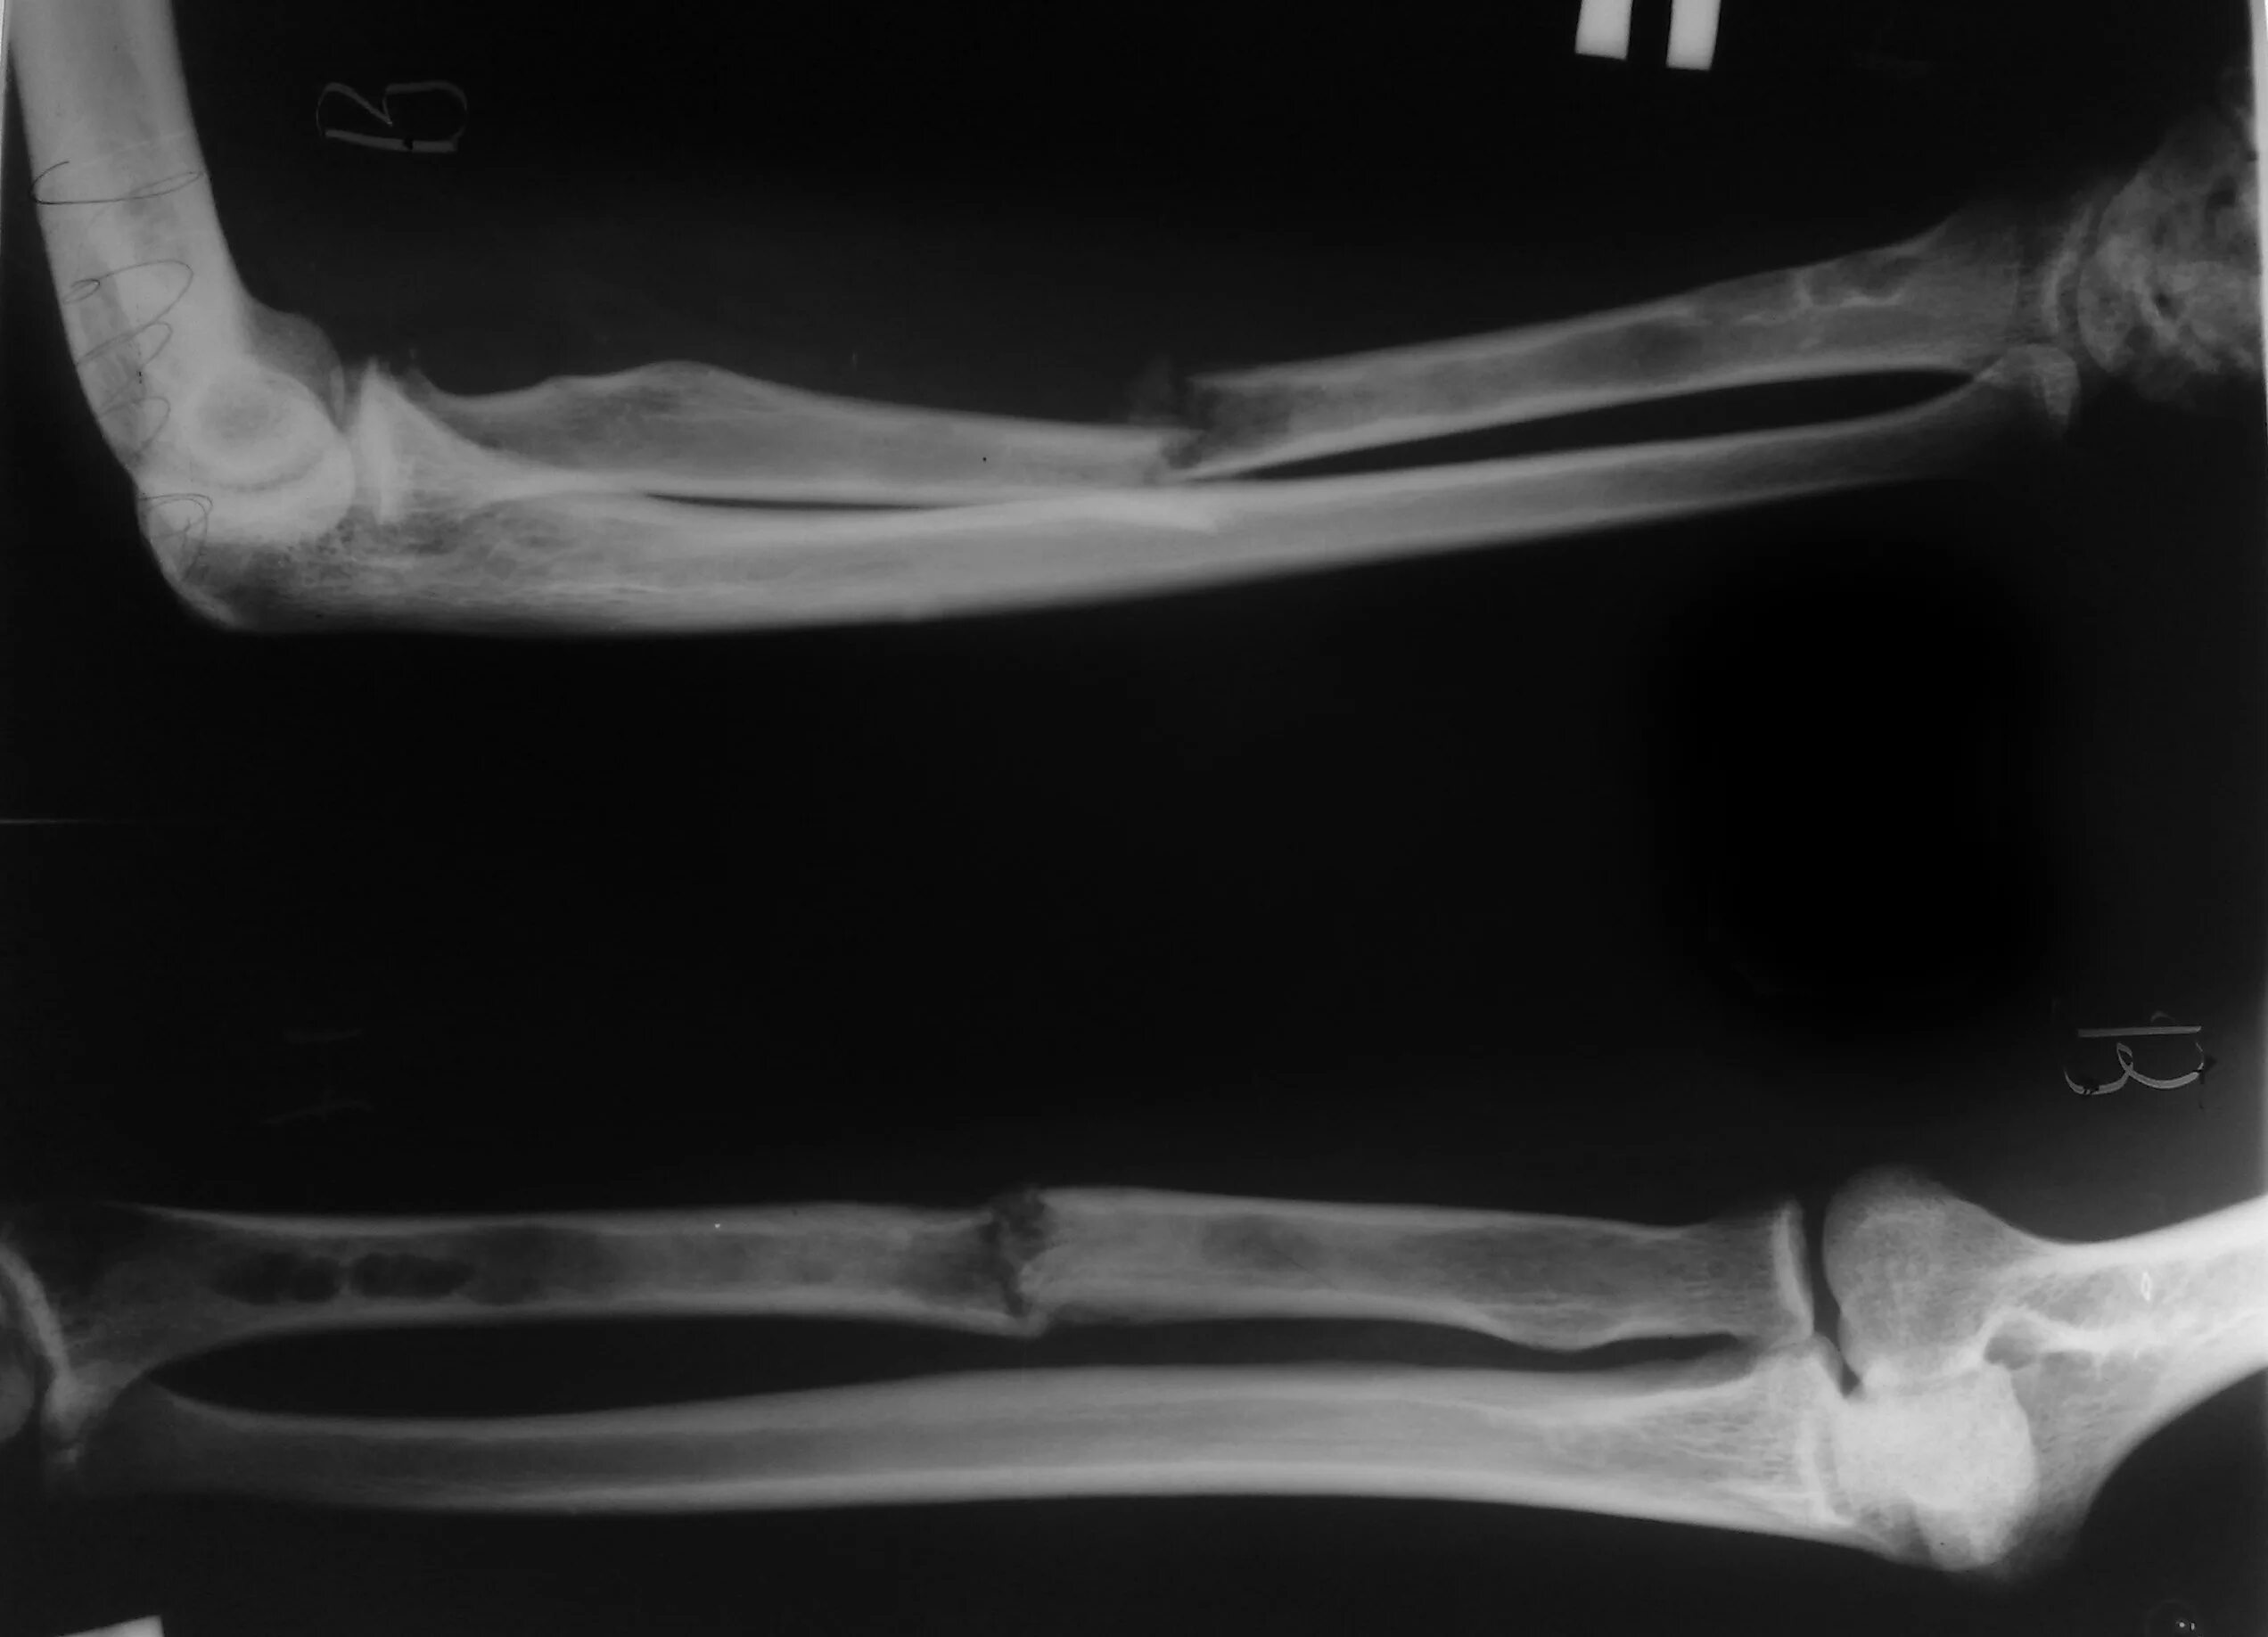

Снимок перелома со смещением